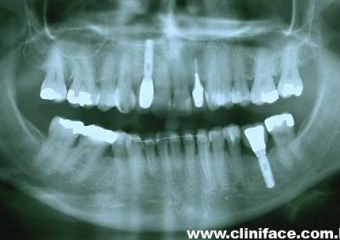

Imagem inicial e final de caso de agenesia dental, reabilitado com implante unitário no elemento 12

Raio X mostrando agenesia do elemento 12, reabilitado com implante e prótese fixa em porcelana

Prótese fixa sobre implante, finalizado em janeiro de 2010